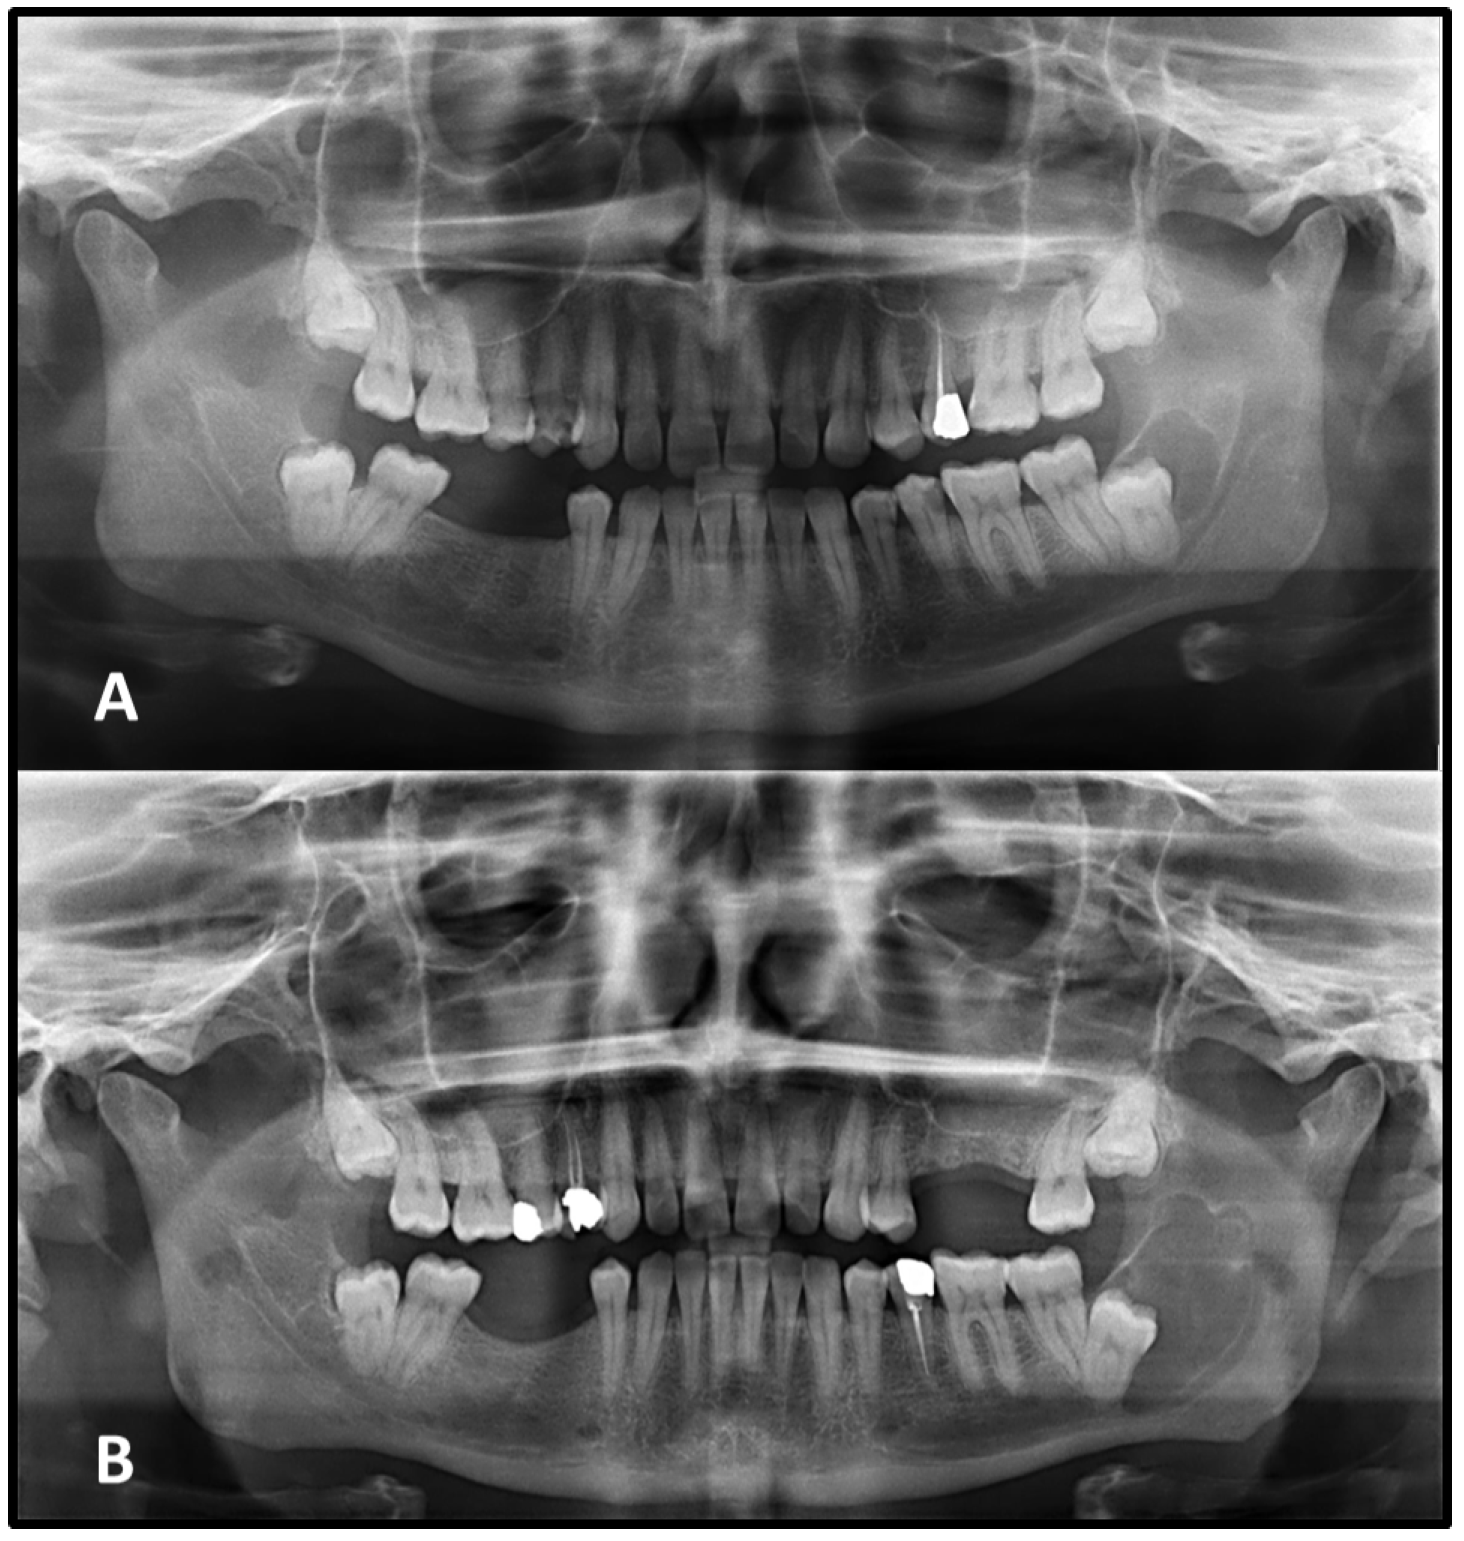

Figure 4).

Figure 5).